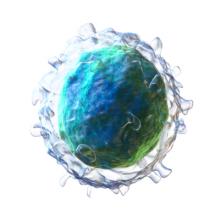

A new type of immunotherapy showed promising results in a small trial done by the MD Anderson Cancer Center. The researchers used an immune cell called a Natural Killer (NK) cell. The NK cells were genetically altered to recognize a protein found on the surface of B cells, a type of immune cell.… more

Immunotherapy is a type of cancer treatment that uses the patient’s own cells to fight against cancer cancer cells. However, not all patients respond to this type of therapy. Our previous news report told about the rare story of a cancer patient who ultimately died from an “invisible” cancer cell… more

About one year ago, a promising form of cancer treatment suffered a serious setback. The treatment is a type of immunotherapy that uses a cancer patient’s own white blood cells to fight the cancer. This is done by adding a gene to the patient’s white blood cells that allows those cells to recognize… more